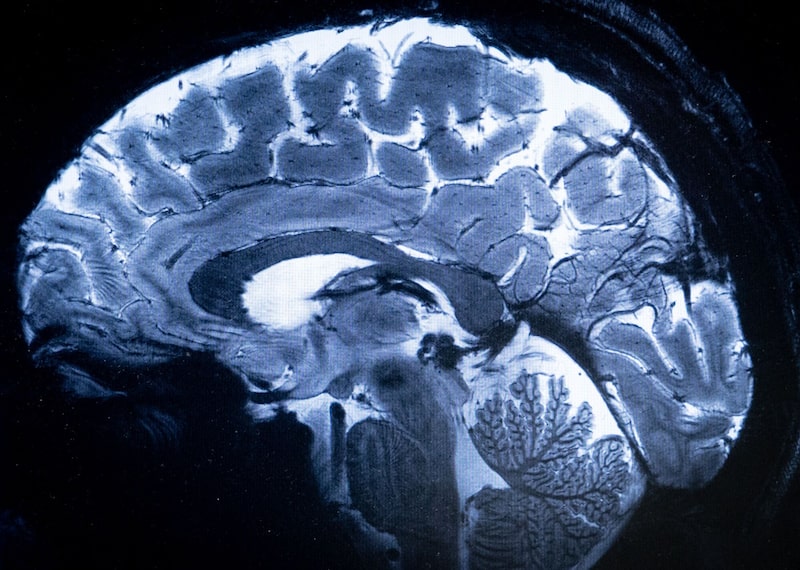

Investigadores chinos utilizaron en marzo interfaces cerebro-ordenador, o BCI, un implante invasivo inalámbrico en un paciente con tetraplejia, informó el periódico en lengua inglesa.

La BCI es una tecnología emergente para ayudar a recuperar la funcionalidad a las personas con parálisis, y Neuralink Corp, cofundada por Elon Musk, está a la vanguardia de esta investigación. El implante utilizado en el ensayo chino es el más pequeño del mundo hasta la fecha, con un diámetro de 26 milímetros y un grosor inferior a 6 milímetros, señala el Global Times, que añade que es más de 100 veces más flexible que el desarrollado por Neuralink.